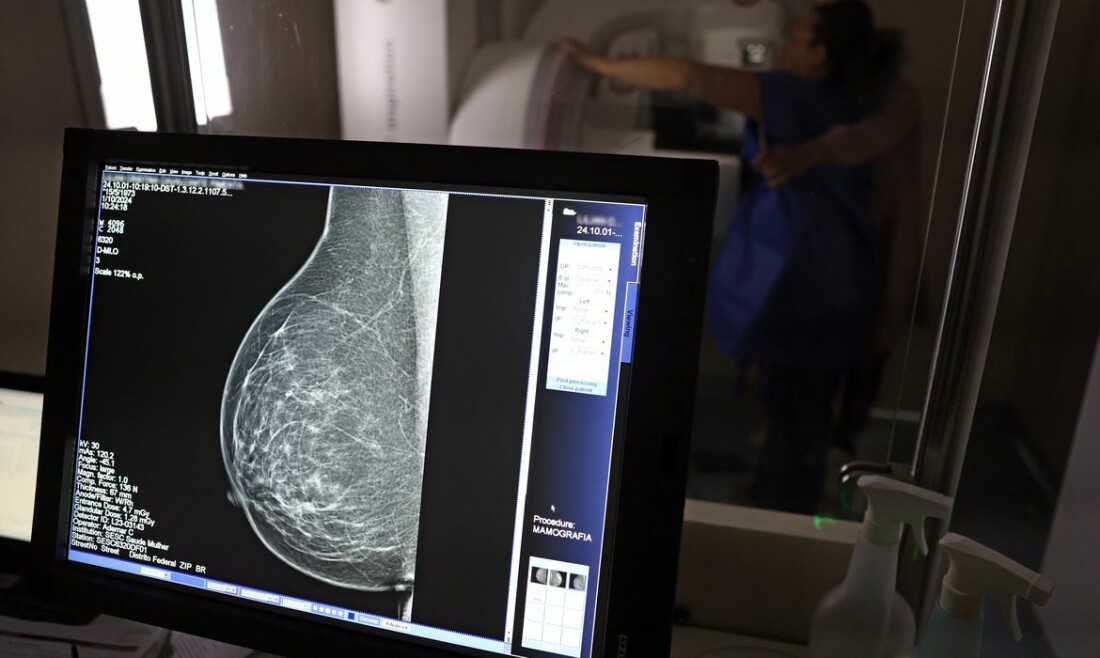

A Advocacia-Geral da República (AGU) informou nesta quinta-feira (20) ter aberto uma ação civil pública contra o médico Lucas Ferreira Mattos, por ele ter dito em postagem nas redes sociais que o exame de mamografia causa câncer de mama.  Mattos, que tem1,3 milhão de seguidores no Instagram e 22 mil do YouTube, fez a declaração em outubro do ano passado, ao responder uma seguidora que o havia questionado sobre o que poderia fazer “pra acabar” com dois nódulos nos seios, que seu médico pessoal havia dito para somente acompanhar com a realização de exames.  "Vamos acompanhar? Acompanhar o quê, se o médico não está fazendo nada para resolver. Ficar fazendo mamografia? Uma mamografia gera uma radiação para a mama equivalente a 200 raio-x. Se aumenta a incidência de câncer de mama por excesso de mamografia. Eu tenho 100% de certeza que seu nódulo benigno é deficiência de iodo”, disse o médico na ocasião, em uma resposta em vídeo.  O caso levou os conselhos regionais de medicina de Minas Gerais e São Paulo a abrirem investigações tendo o médico como alvo. O Instituto Nacional do Câncer (Inca) também informou, à época, não haver evidência de que a mamografia possa causar câncer de mama e que, pelo contrário, o exame previne a doença.  Agora, a AGU pede que o médico seja condenado a pagar R$ 300 mil em indenização por danos morais coletivos, por ter disseminado informação de saúde falsa. O órgão pede ainda que ele seja obrigado a apagar as postagens com a desinformação e a publicar conteúdo pedagógico e informativo sobre a mamografia produzido pelo Ministério da Saúde.  O material deve ser republicado durante a campanha do Outubro Rosa, que ocorre todos os anos para conscientiza sobre a importância do exame preventivo, segundo pede a AGU na ação. Em nota, a AGU disse que “a propagação de desinformação sobre o tema pode desestimular mulheres a fazerem o exame preventivo, afetando as políticas públicas de enfrentamento ao câncer de mama”.  O órgão anexou ao processo nota técnica do Ministério da Saúde segundo a qual “é recomendado que mulheres de 50 a 69 anos, de risco padrão, façam uma mamografia de rastreamento a cada dois anos. Esse exame pode ajudar a identificar o câncer antes de a pessoa ter sintomas”.  A Agência Brasil tenta contato com o médico para comentar o processo. Após a repercussão do caso, em outubro do ano passado, Mattos publicou novo vídeo afirmando que suas declarações haviam sido distorcidas. “Eu nunca postei aqui no meu Instagram que câncer de mama não existe. Eu falei no meu Instagram que radiação é um dos fatores que causa câncer, assim como qualquer outro tipo de câncer”, disse na ocasião.  Relacionadas Justiça proíbe divulgação de informações falsas sobre mamografia Entidades médicas pedem faixa etária maior para mamografia de rastreio Periodicidade de mamografias divide médicos e autoridades de saúde